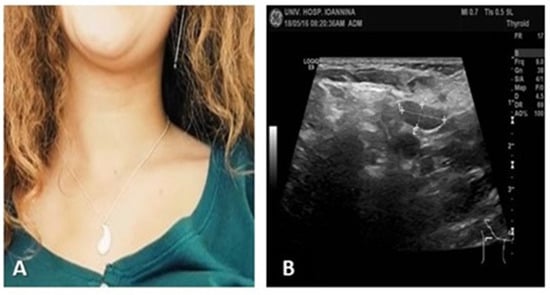

At one-month follow-up, the patient was asymptomatic (Figure 5A), with improved appetite and weight gain. There were no palpable cervical or supraclavicular lymph nodes, and ultrasound findings were near normal (Figure 5B). Leukopenia had resolved, although mild lymphopenia persisted for several months.

Figure 5.

(A) Patient in follow-up, without lymphadenopathy; (B) ultrasound: 2 small lymph nodes with normal architecture and echo structure.